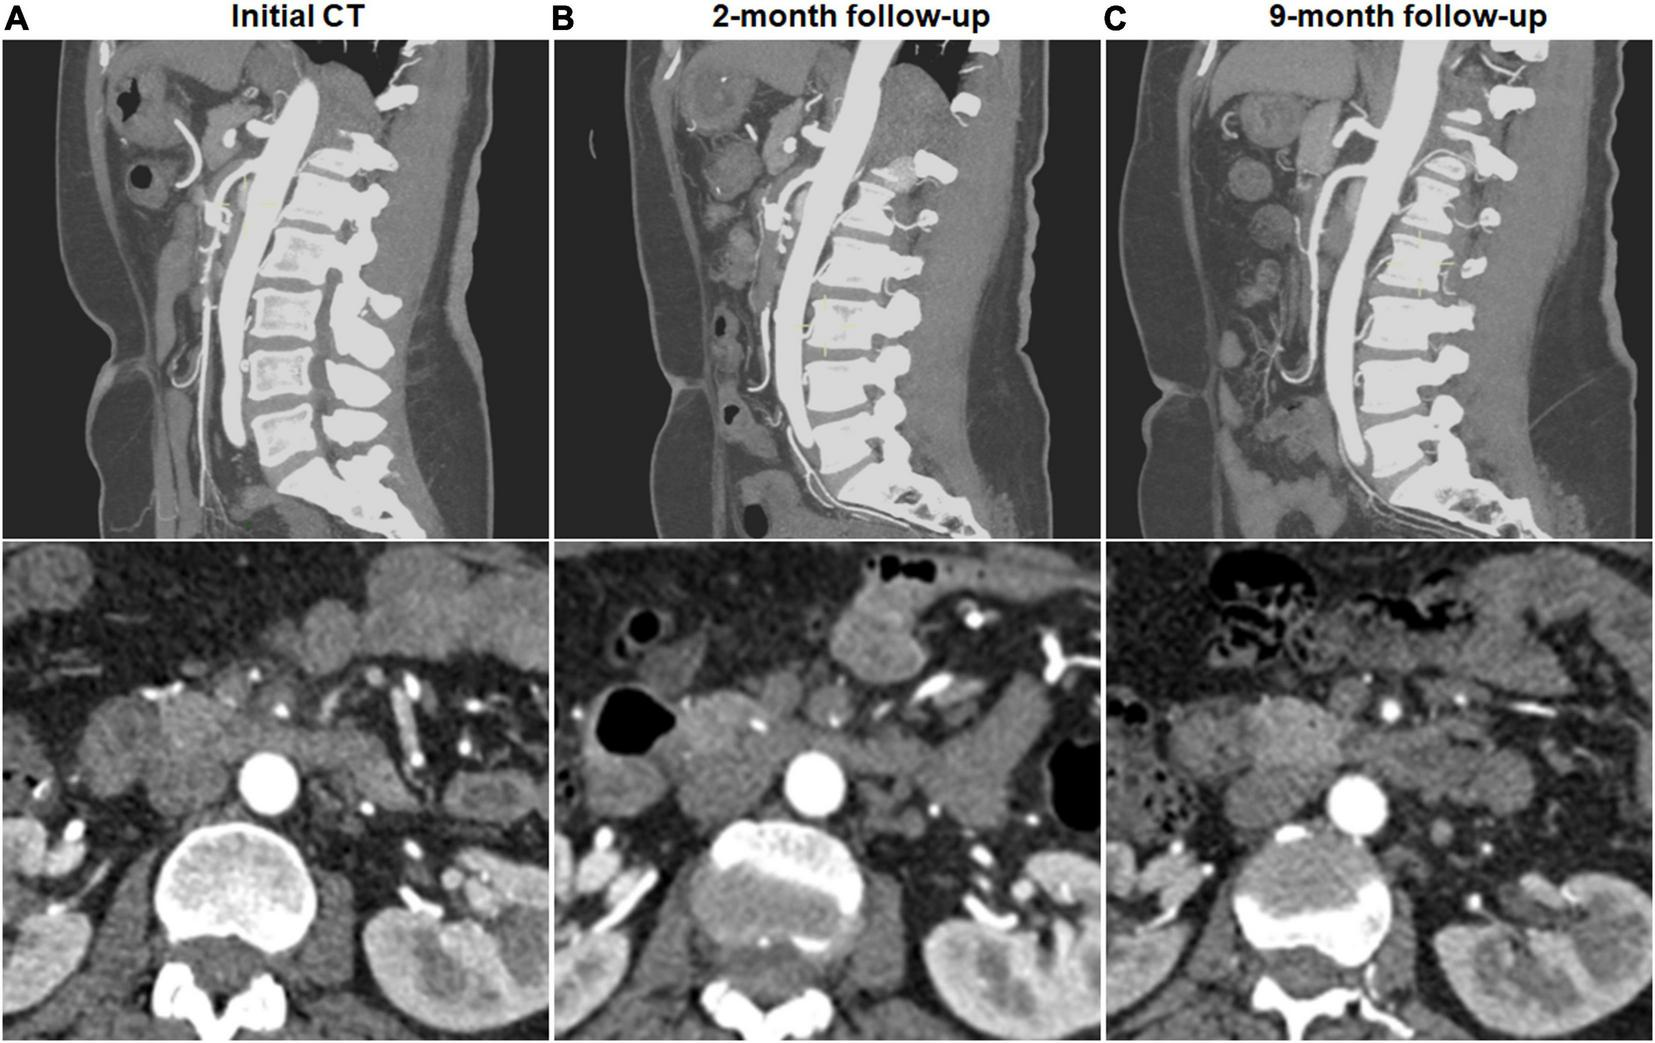

Complete remodeling on CTA occurred in 1 (7.1%) of 14 type I dissections of patent FL with both entry and re-entry, 1 (3.0%) of 33 type II dissections of patent “cul-de-sac” shaped FL without re-entry, 14 (58.3%) of 24 type III dissections of thrombosed FL with ULP (Figure 2) and 14 (87.5%) of 16 type IV dissections of the completely thrombosed FL without ULP (Figure 3). In 14 type III lesions, the mean diameter of TL increased from 3.2 (3.0; 4.1) mm on initial CT to 5.8 ± 1.0 mm on follow-up CT (p < 0.001). In 14 type IV lesions, the mean diameter of TL was recovered from 4.3 ± 1.1 mm on initial CT to 6.6 ± 1.0 mm on follow-up CT (p < 0.001). Thus, thrombus in the FL of type III and IV lesions may contribute to the process of the complete wall remodeling.

FIGURE 2

Complete remodeling of type III spontaneous isolated superior mesenteric artery dissection on follow-up computed tomography (CT) angiography. (A) Initial CT angiography showed the thrombosed false lumen with ulcer-like projection (ULP) in a 52-year-old woman. (B) Two months later, stenosis of true lumen was aggravated with thrombosis of false lumen and ULP. (C) Nine months later, ULP disappeared and thrombosis in the false lumen was completely resolved.